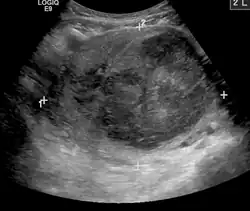

A very large (9 cm or 3.5 in) fibroid of the uterus causing pelvic congestion on US

Chronic pelvic pain

• Veins have one-way valves that help blood flow toward the heart. If the valves are weak or damaged, blood can pool in veins, making them swell. When this happens near the pelvis, it is called pelvic congestion syndrome, which can lead to chronic pain beneath the level of the belly button.

• Pelvic congestion syndrome usually affects women who have previously been pregnant, because the ovarian veins and pelvic veins had widened to accommodate the increased blood flow from the uterus during pregnancy. After the pregnancy, some of these veins remain enlarged and fail to return to their previous size, causing them to weaken and allowing blood to pool.[42]

• An interventional radiologist can offer a minimally invasive treatment option for pelvic congestion syndrome: ovarian vein embolization

• Ovarian vein embolization is a same-day treatment which takes place in an interventional radiology suite. The interventional radiologist gains access through a large vein in the groin, called the femoral vein, by using a small catheter, which is a flexible tube like a strand of spaghetti. The catheter is moved through the vein to the enlarged pelvic veins, allowing the introduction of embolic agents, which are medications that cause the vein to seal off and relieve the painful pressure.[43]